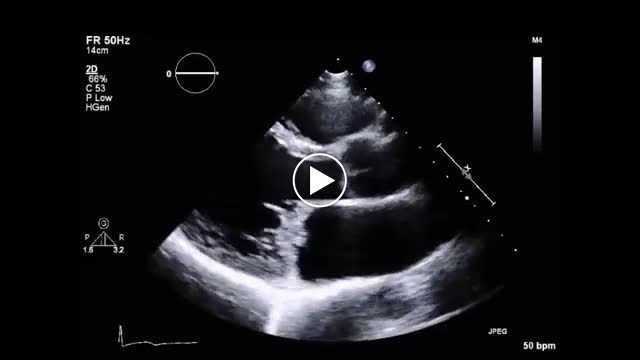

• 図7 click and late systolic murmur b